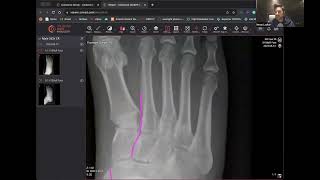

3:56

Can you see any fracture? Plain Film X-Ray by Dr. Imran Lasker Case 6/10 #xray #radiologyedu

Radiology Seminars

Shared 8 months ago

47 views